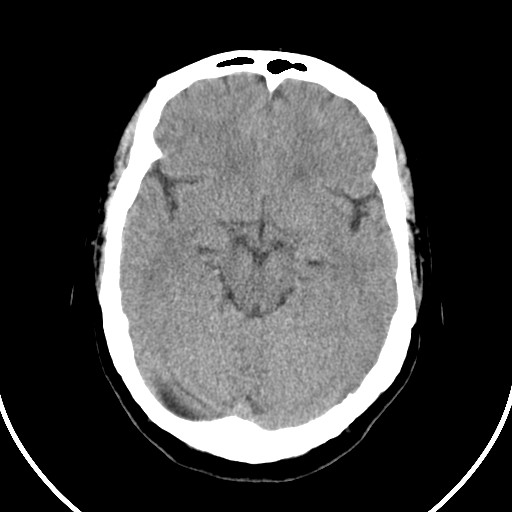

标题: CT21850:女,56岁,右中指淤肿,右手麻痹1天

女,56岁,右中指淤肿,右手麻痹1天

右侧侧脑室旁脑白质腔隙性脑梗死。

右侧基底节多发小梗塞

作者: huangyinshan    时间: 2009-8-25 15:37

右基底结区腔梗

右侧基底节区腔隙性脑梗塞

右侧基底节多发腔梗!

双侧侧脑室额角旁对称性略低密度影,边缘模糊,无占位效应,考虑轻度脑白质稀疏症(病人有高血压吗).,右枕叶低密度影多为伪影,不放心薄扫一下.

考虑脑白质病。

考虑脑白质病